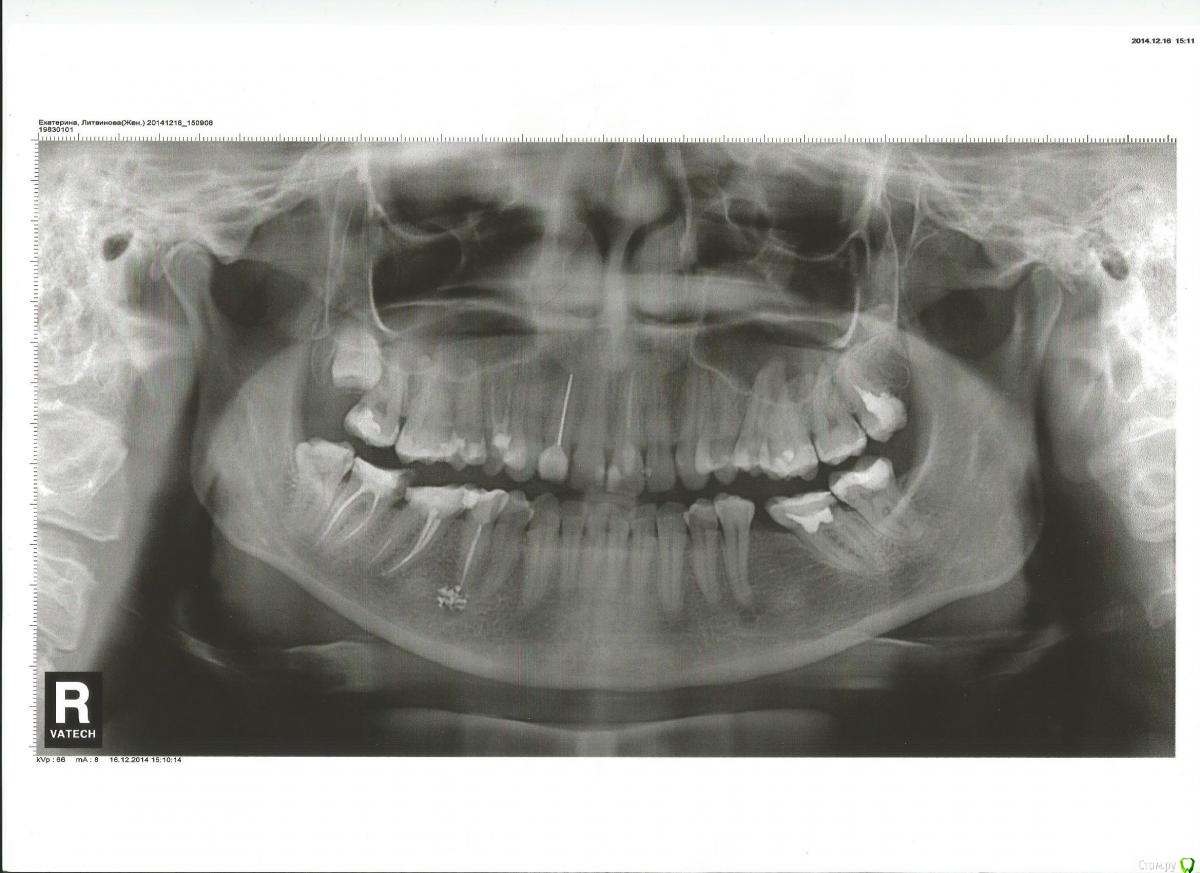

Екатерина Литвинова Опубликовано 16 марта, 2015 Автор Поделиться Опубликовано 16 марта, 2015 (изменено) Прикрепляю панорамный снимок,сделанный в декабре 2014,перед удалением зуба мудрости Изменено 16 марта, 2015 пользователем Екатерина Литвинова Ссылка на комментарий